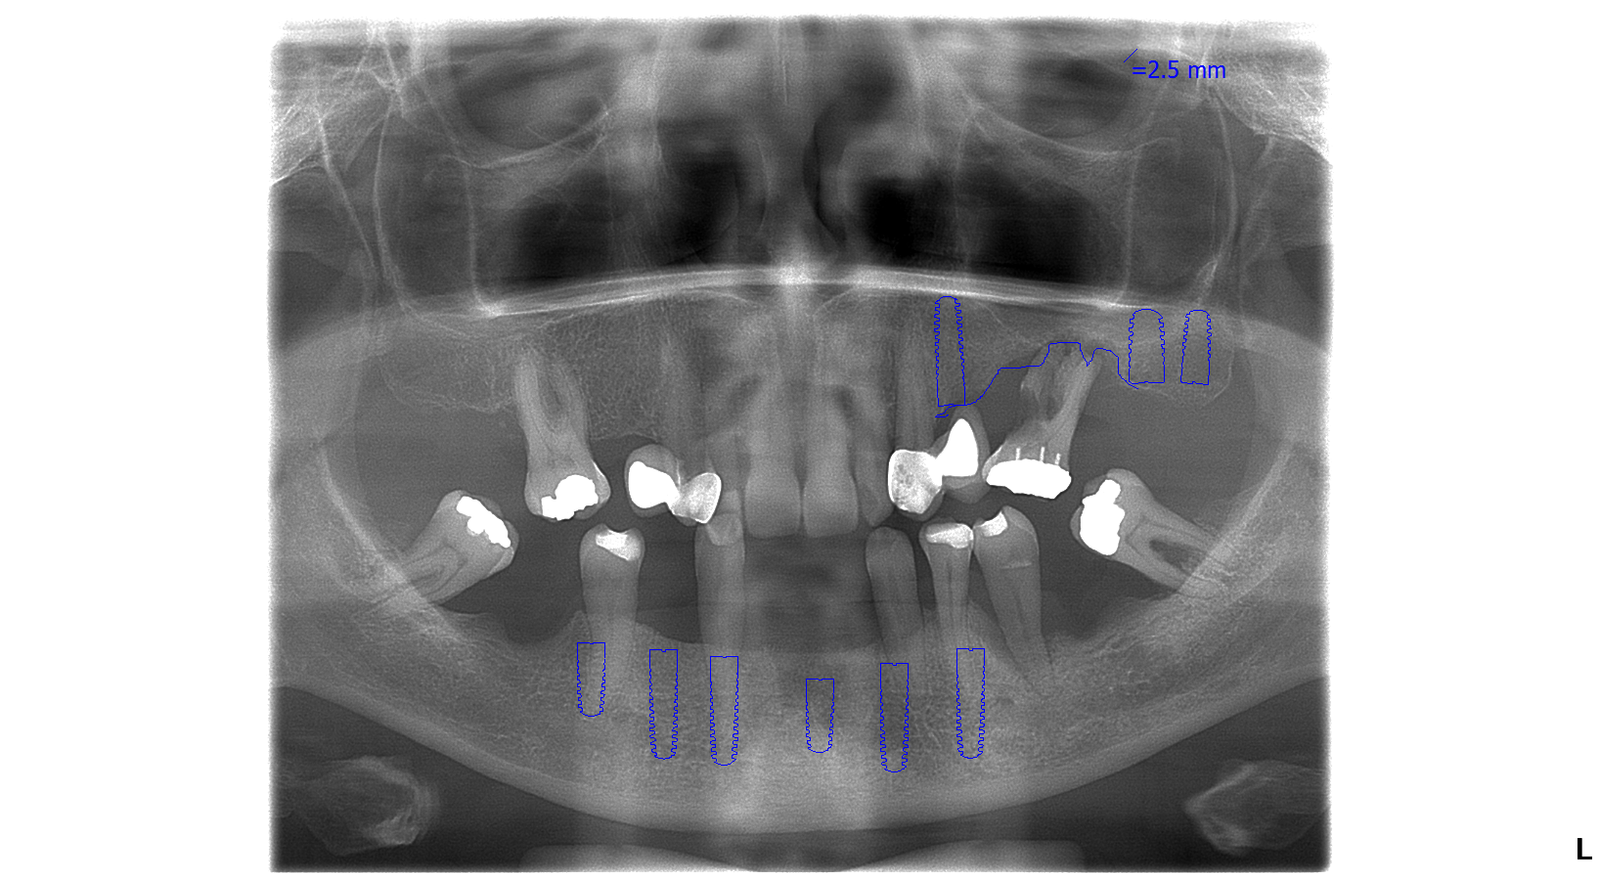

vrchná čeľusť:     3 zubné implantáty, sinus lift, 8 zirkónových koruniek, 1 endodoncia –  ošetrenie koreňových kanálikov

spodná čeľusť:     6 zubných implantátov, 12 členný fixný keramický mostík

Najprv sa pacientka rozhodla pre ošetrenie spodnej čeľuste, kde bolo potrebných 6 zubných implantátov. Po implantácii bol pacientke nasadený dočasný, titánom vystužený mostík. Ten slúži ako dočasná zubná náhrada počas doby hojenia.

Snímok pred ošetrením